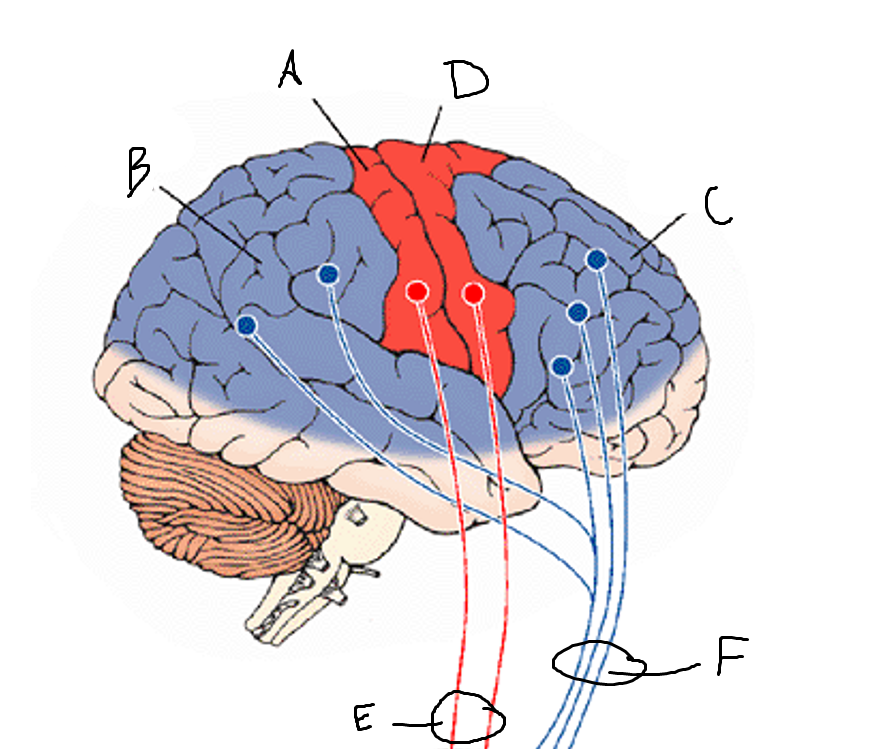

basal ganglia

A

somatosensory cortex

B

parietal association cortex

C

frontal and prefrontal cortices

D

primary motor cortex

E (where are the projections?)

putamen

F (where are the projections?)

caudate